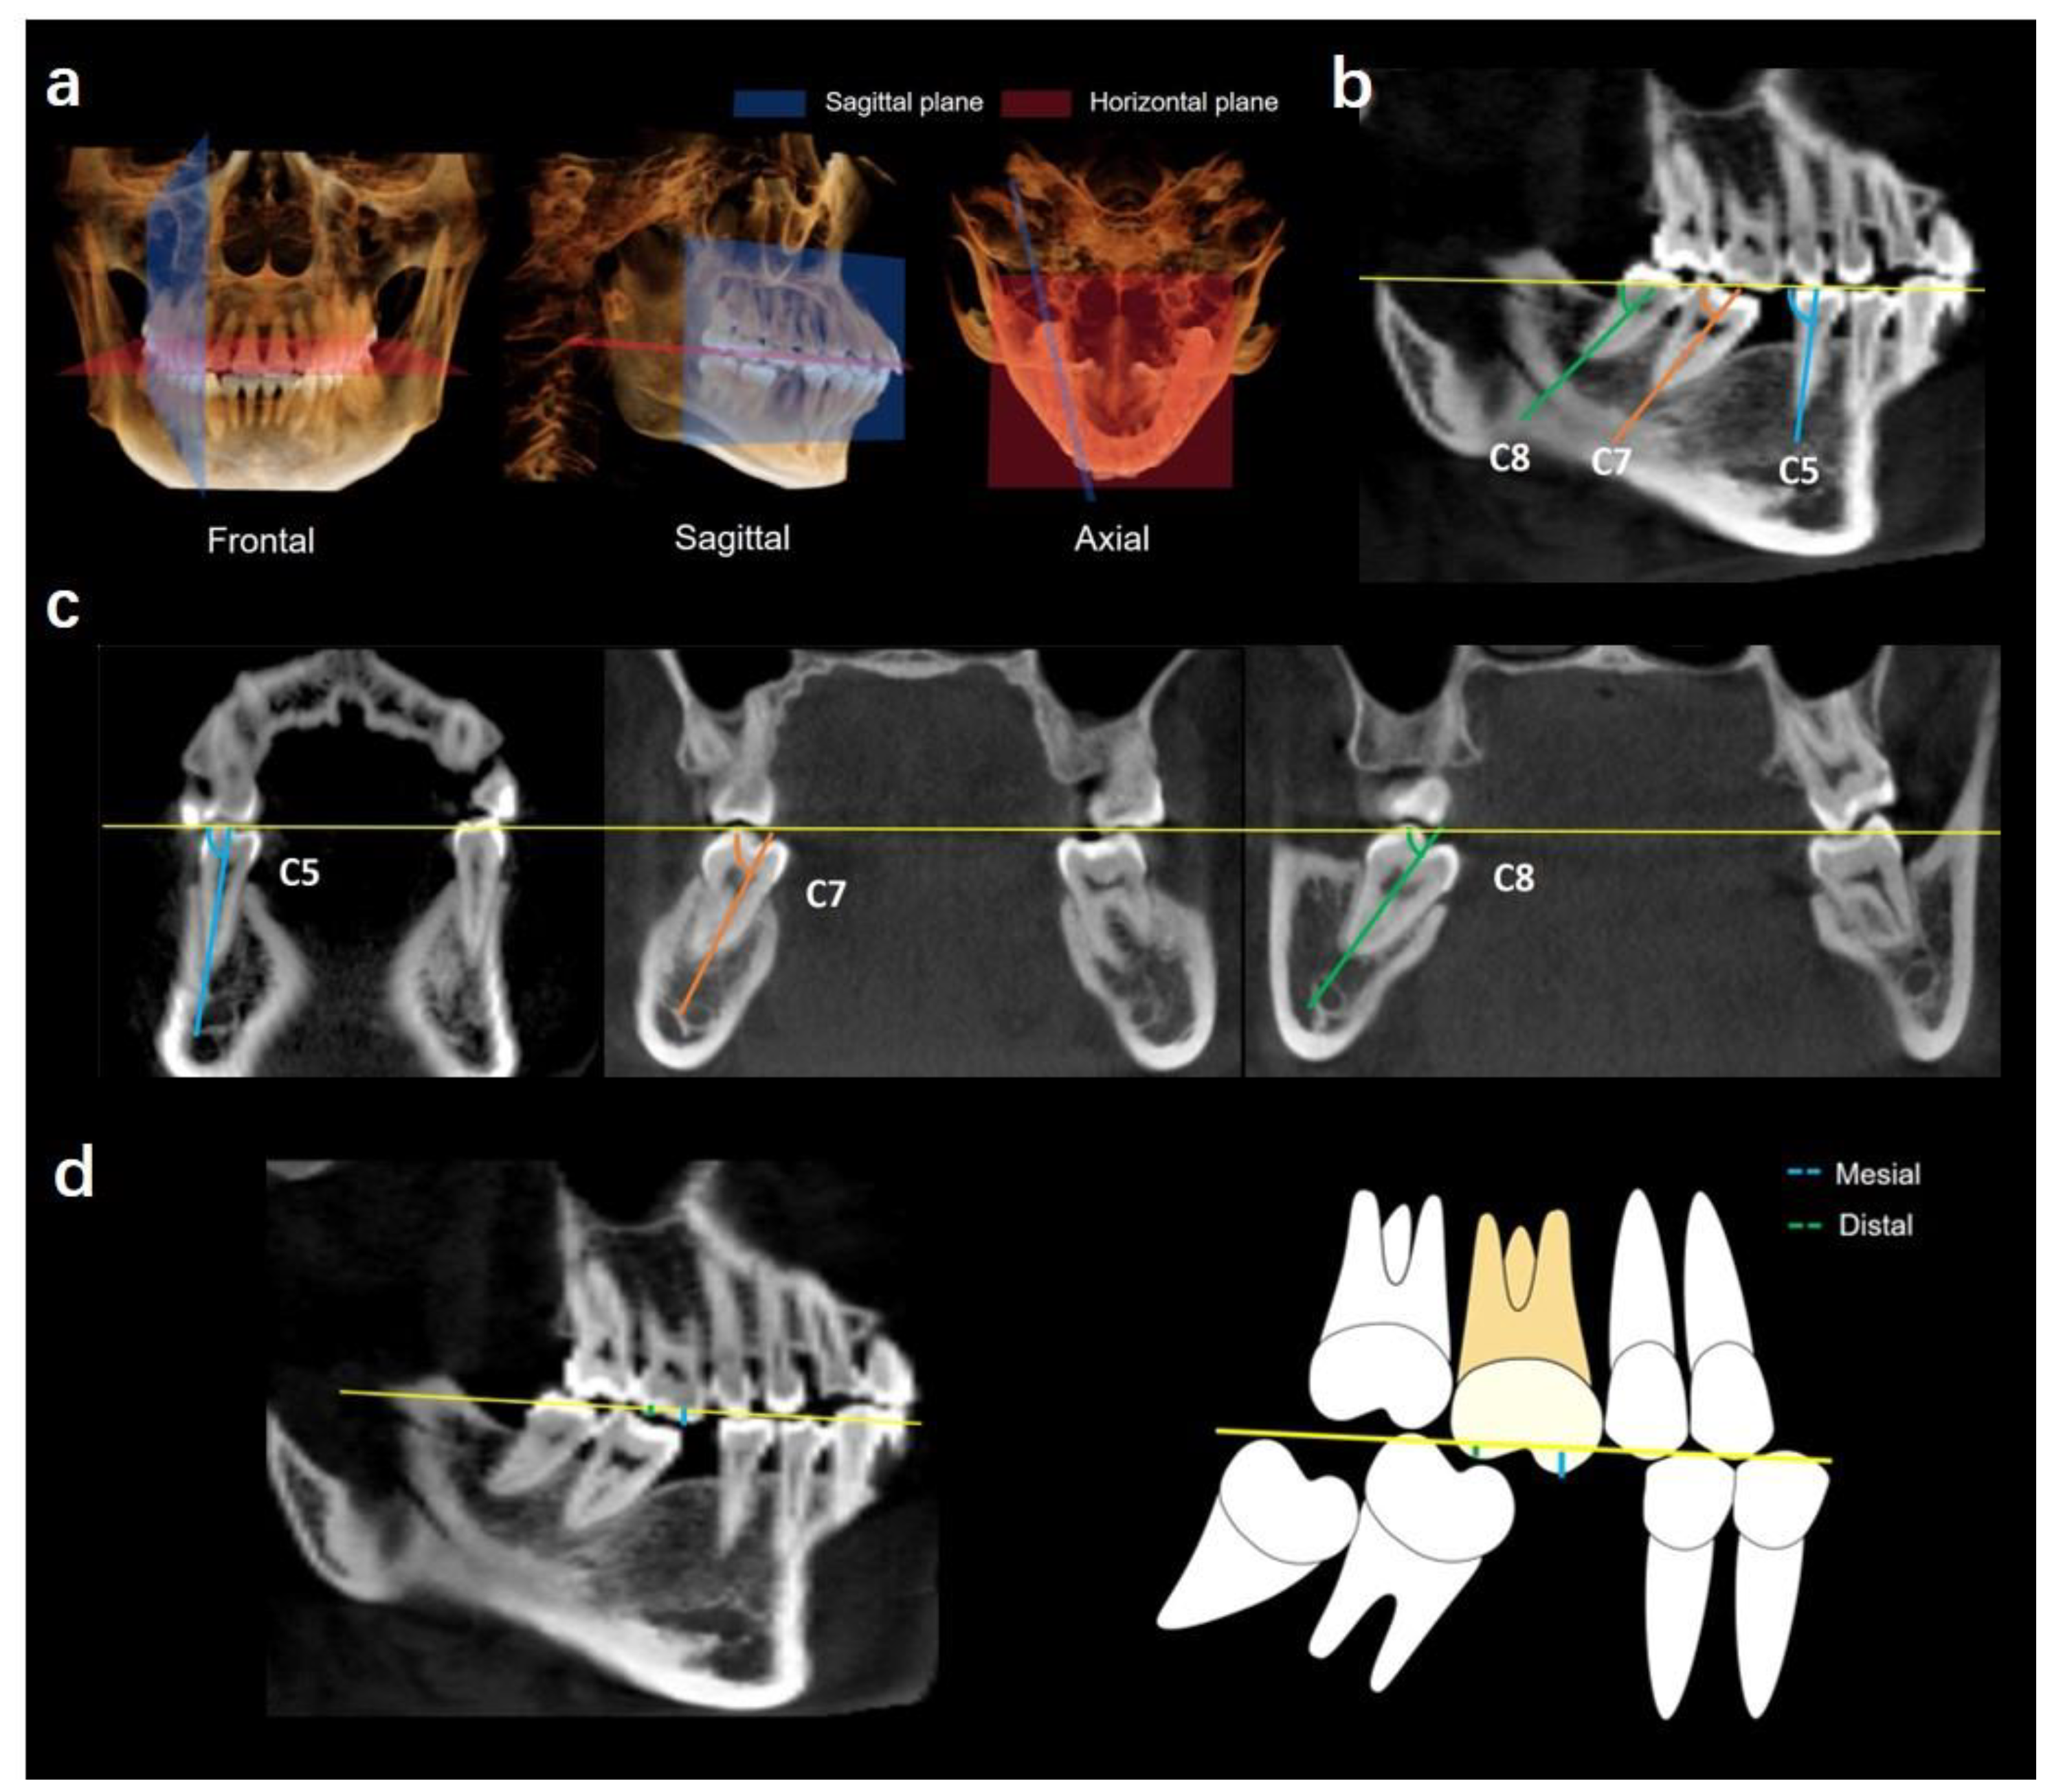

2.1. Determination of Coordinate Planes

2.2. Measurements

2.2.1. Angulations of Bilateral Mandibular Posterior Teeth

Mesiodistal Angulation

Buccolingual Angulation

2.2.2. Extrusion of Maxillary First Molars

2.2.3. Alveolar Bone Loss in the Missing Tooth Region

Vertical Alveolar Bone Loss in Missing Tooth Region

Horizontal Alveolar Bone Loss in Missing Tooth Region